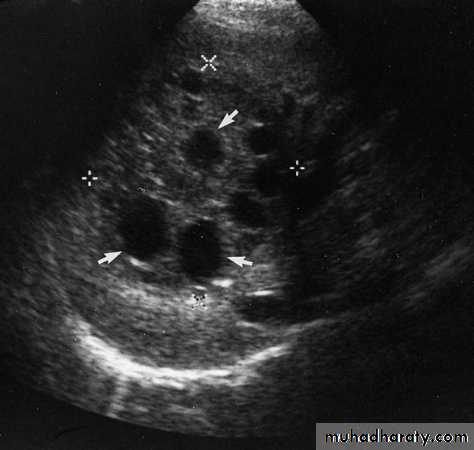

Hydatid cysts may be single or multiple; a few show calcified walls. Daughter cysts may be seen within a main cyst at both US and CT.